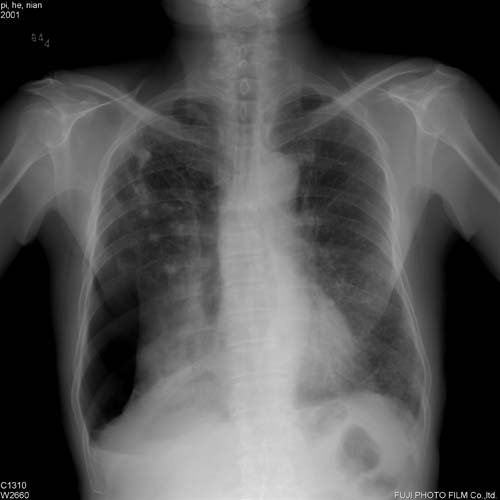

此病人咳嗽\胸闷一周,伴随发热两天.

右肺感染伴陈旧性结核;肺气肿;右侧自发性液气胸。

右侧气胸部分气体位于右上纵隔胸膜腔,右下肺萎陷且密度不均匀还应考虑肺内或者胸膜病变,建议结合侧位片,右上肺结核以纤维增殖灶和钙化灶为主,

另外,纵隔气肿.

右肺感染伴陈旧性结核;肺气肿;右侧自发性液气胸(多房性,胸膜粘连所至)